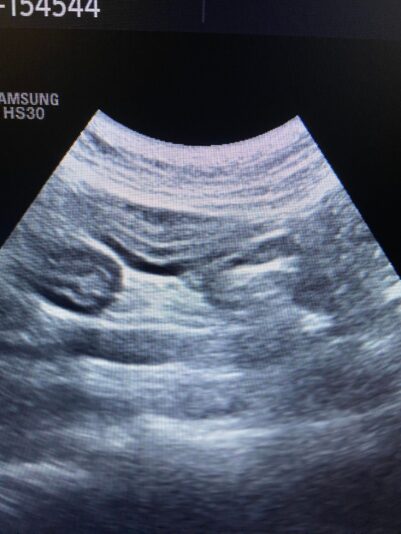

these are the photos of the bloodwork and from the ultrasound

This post is about a patient of mine that came to me on Wednesday.

General information and history: Cat, male, not castrated, 11 years old with different behaviour since 3 days. According with the owners, the cat didnt want to eat and drink for 3 days. Also he wasnt active and he was hiding. The owners didnt have…